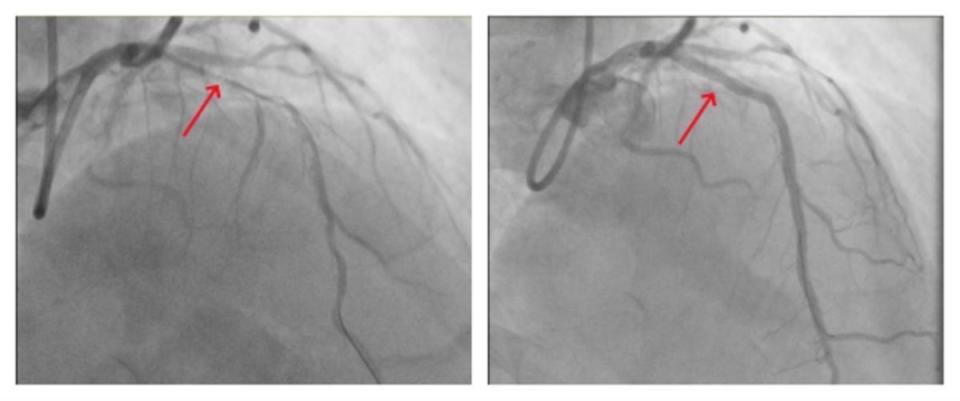

图片术前血管严重狭窄(左),术后恢复血流通畅(右)

4月8日,吴爹爹的手术开始。宋丹主任、刘华云主任带领手术团队,在腔内影像“透视眼”的帮助下,确认了钙化病变的位置、大小和程度。随后,通过发射器产生的冲击波,借助球囊将血管内的钙化“石头”隔空震碎。最后,在前降支血管植入心脏支架并充分撑开,成功打通“生命线”,手术历时2个小时。